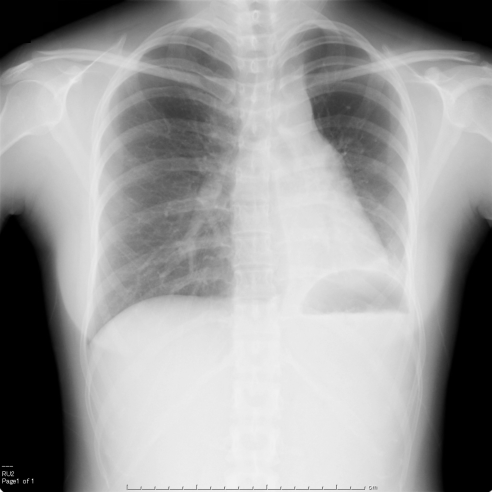

右中葉の無気肺の胸部単純X線写真

胸部正面写真で右心下縁(右第2弓)のシルエットが消失し、淡い陰影を認める(右第2弓でシルエットサイン陽性)。